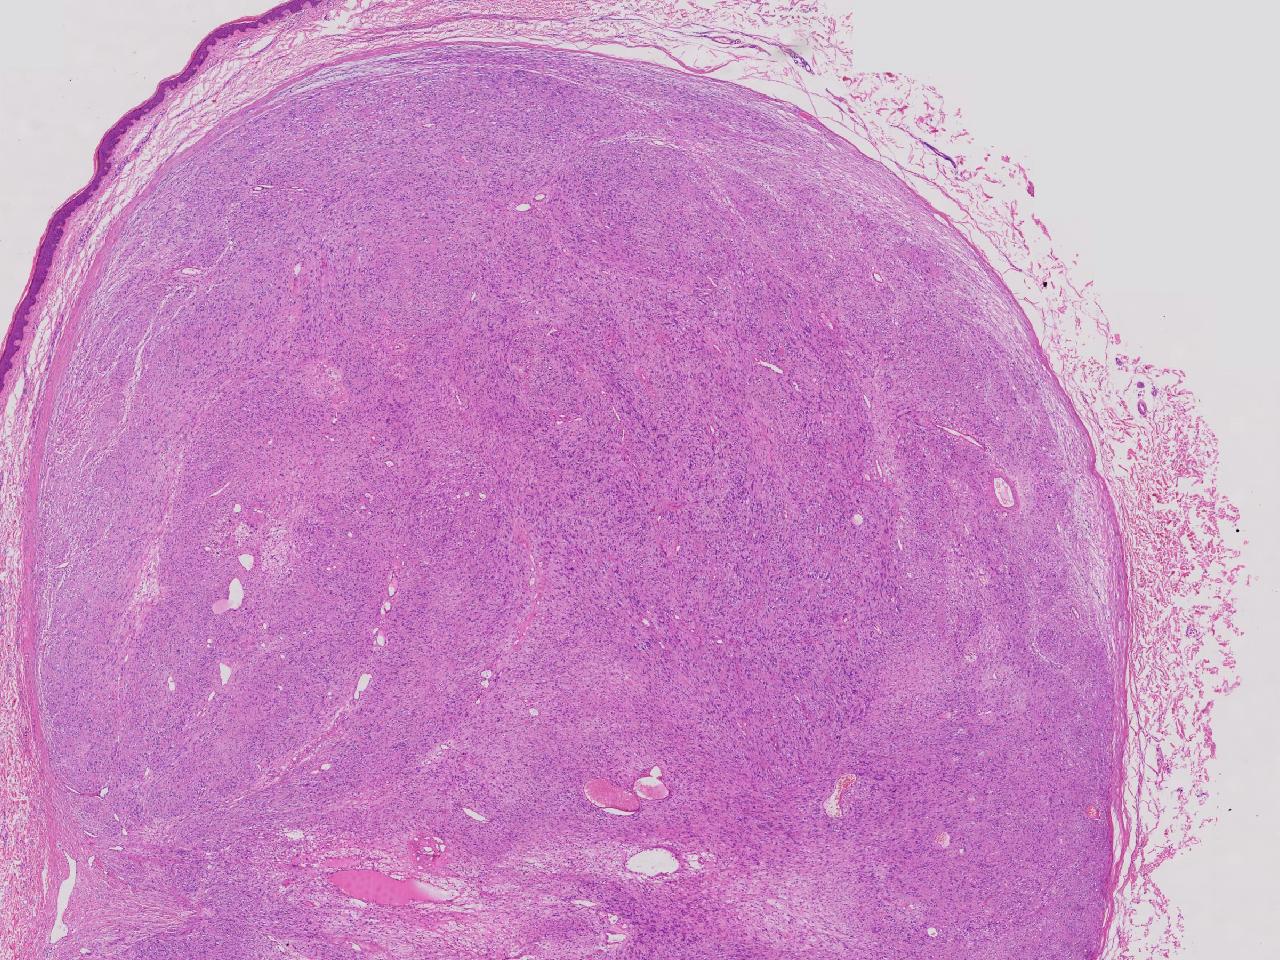

血管平滑肌瘤? 其他?

性别

女

年龄

76岁

临床诊断

右侧腰臀部皮下肿物

一般病史

右侧腰臀部皮下肿物1年余,无明显不适,逐渐增大。

标本名称

大体所见

卵圆形肿物一个,直径1.6厘米,上附皮肤。肿物切面灰黄实性,质中等。

图1

考虑:结节性筋膜炎

神经鞘瘤。